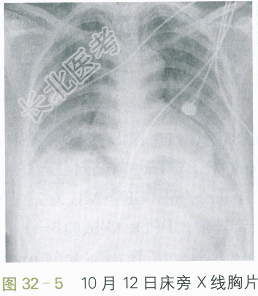

患者之后出现右下肢轻微肿胀,D-二聚体3.2mg/L,予以低分子肝素(依诺肝素)治疗。12月4日出现皮下气肿,及时停用无创呼吸机。12月8日血胆固醇59mg/L,给予阿托伐他汀10mgqd。住院期间还予口腔护理防治真菌感染等,患者咳嗽轻,有咳白色黏液痰,稍活动有气急。查体:呼吸平稳,两肺未闻及干湿性啰音,HR80次/min,律齐,四肢肌力可,无肌肉萎缩。影像学示两肺仍呈弥漫性炎症,病灶吸收慢,伴纤维化形成(见图32-5、图32-6)。于12月25日好转出院,吸氧2L/min时PaO₂为62mmHg。1个月后不吸氧时,PaO₂为68mmHg。